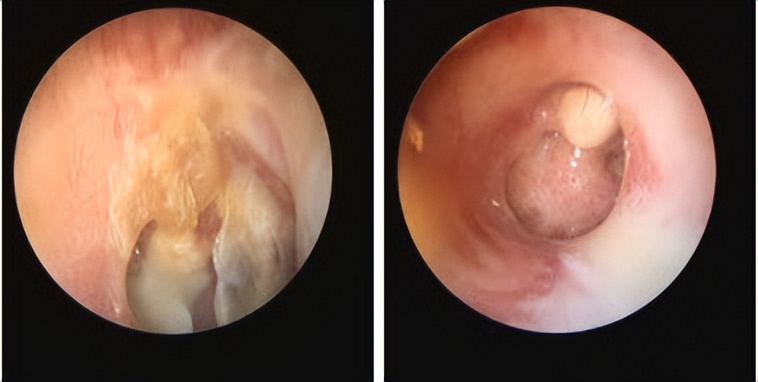

最近就有一位佛山禅城的患者找到耳鼻喉郑立岗医生,患者左侧鼓膜大穿孔,听力非常差。

这次做的是全麻耳内镜中耳炎微创手术,插管全麻后就开始了手术。在耳内镜下不用做任何的体表切口,直接翻起外耳道鼓膜皮瓣,翻起皮瓣后可以看到患者的砧镫关节是断裂的,镫骨底板上结构也是基本破坏没有了,镫骨底板完整,活动好。取出患者残余的砧骨和锤骨后,用钛质全听骨重建了听骨链,取合适大小的耳屏软骨修剪后修补了鼓膜。鼓膜修补好后检查了两遍确认没问题后就结束了手术。术后查房患者无明显的不适,无手术相关的并发症。